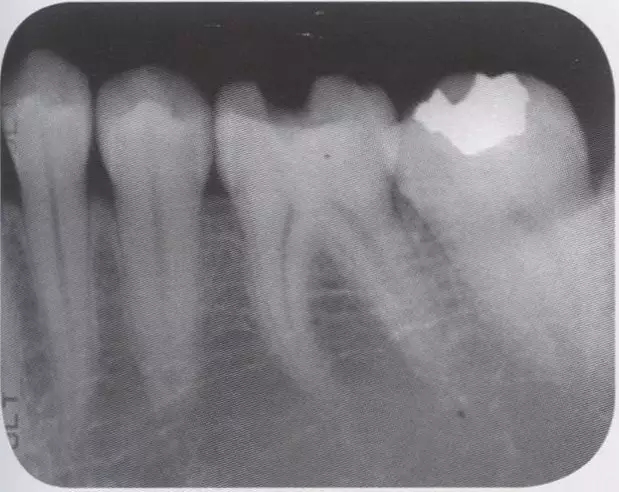

1、術前拍攝牙片,根據(jù)牙根的傾斜判斷有沒有引起鄰牙根間隙過窄的情況。若沒有傾斜,就是簡單病例。

圖1 智齒向遠中傾斜病例

圖2 智齒嵌入被處理牙鄰接面的倒凹,即便分離成功,成形范圍也會變大。

圖3 鄰接面成形困難的病例。如圖所示右下7近中傾斜,窩洞成形的遠中側(cè)有缺損(上左),所以遠中部需要在齦下做很深的成形(上右),因而選擇在遠中先進行樹脂填充后(上右)。進行MO窩洞修整后做全瓷嵌體試戴(下)。